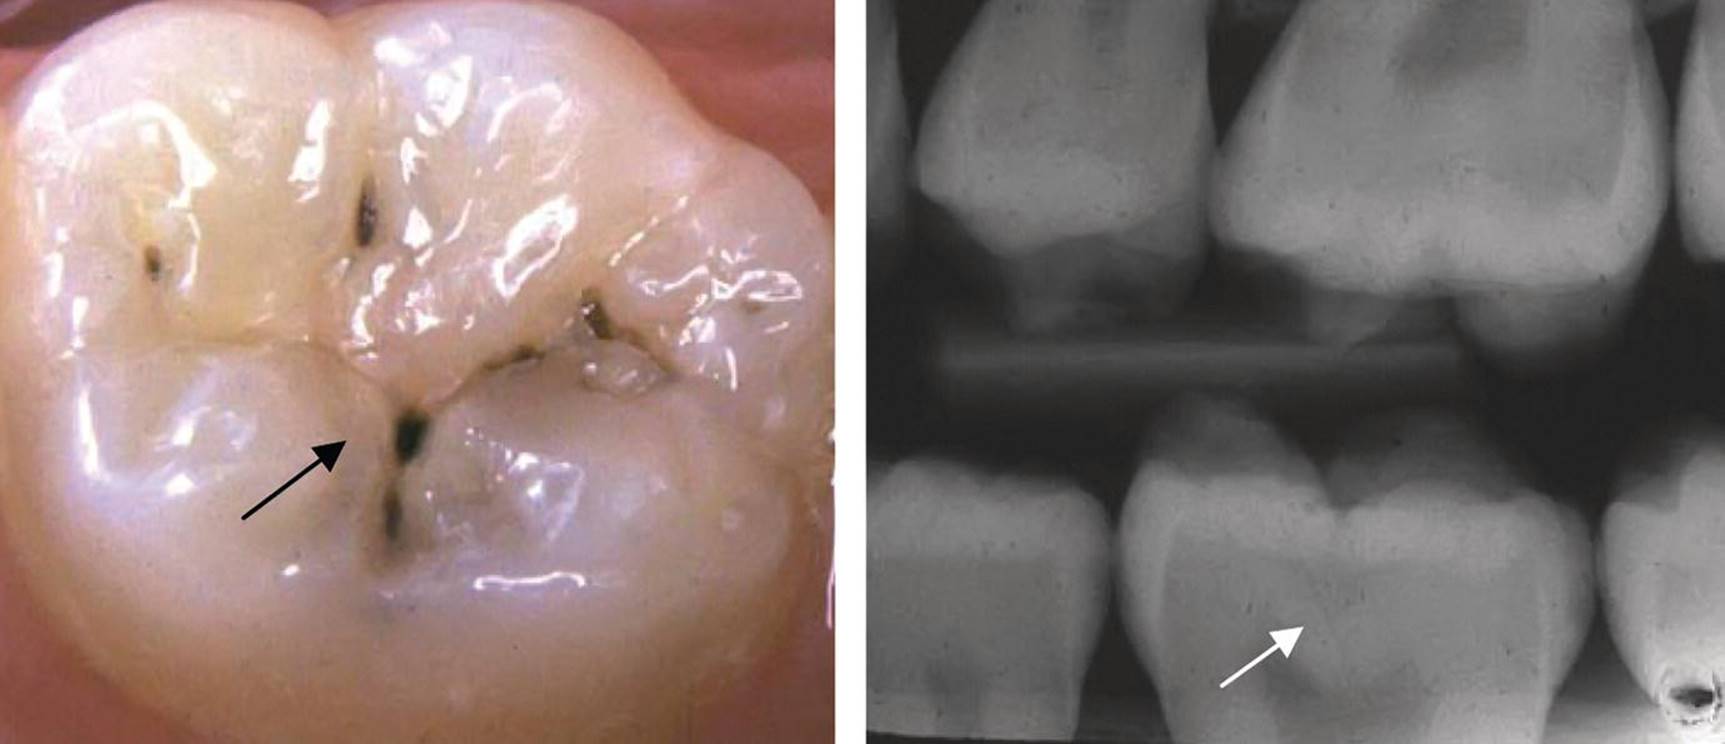

The discolored fissure often poses diagnostic challenges. A discolored fissure does not necessarily indicate an active caries process. To discriminate between active and inactive or arrested lesions, the following characteristics may help:

· Active lesions are most frequently seen in erupting and newly erupted teeth in children with other signs of caries activity in the dentition. The discoloration is usually opaque, whitish, or light brownish. Softened enamel at the entrance of the fissure from gentle tactile probing is indicative of an active lesion. When the discoloration also involves obvious loss of continuity of the enamel surface (clinical cavity), bitewing examination frequently reveals a radiolucency in the dentin (Figure 12.5). Many borderline cases can be difficult to diagnose. For these cases, bitewing radiography is a valuable tool for assessing possible dentin involvement (Figure 12.6a,b).

· Inactive lesions are usually seen in “older” teeth in adolescents with no signs of caries activity. The discoloration is dark brown or black and the surface is hard on careful probing (Figure 12.6c). There is usually no substantial dentin involvement.

Figure 12.5 A small but obvious occlusal cavity in the central fossa of a permanent first molar (arrow). The borders around the cavity are whitish and rough in texture suggesting an active caries process. There is a shadow from underlying dentin caries. The radiograph reveals a substantial radiolucency in the dentin (arrow).

Figure 12.6 (a) Light brown discolored fissures in a permanent first molar of an 8‐year‐old. The enamel around the central fossa is whitish and there is softened enamel at the entrance of the fissure indicating an active lesion (arrow). (b) The radiograph reveals radiolucency in the dentin (arrow). (c) Dark brown/black discolored fissures in a permanent first molar of a 19‐year‐old with a low caries activity. The fissures are hard on probing indicating an arrested (inactive) lesion.